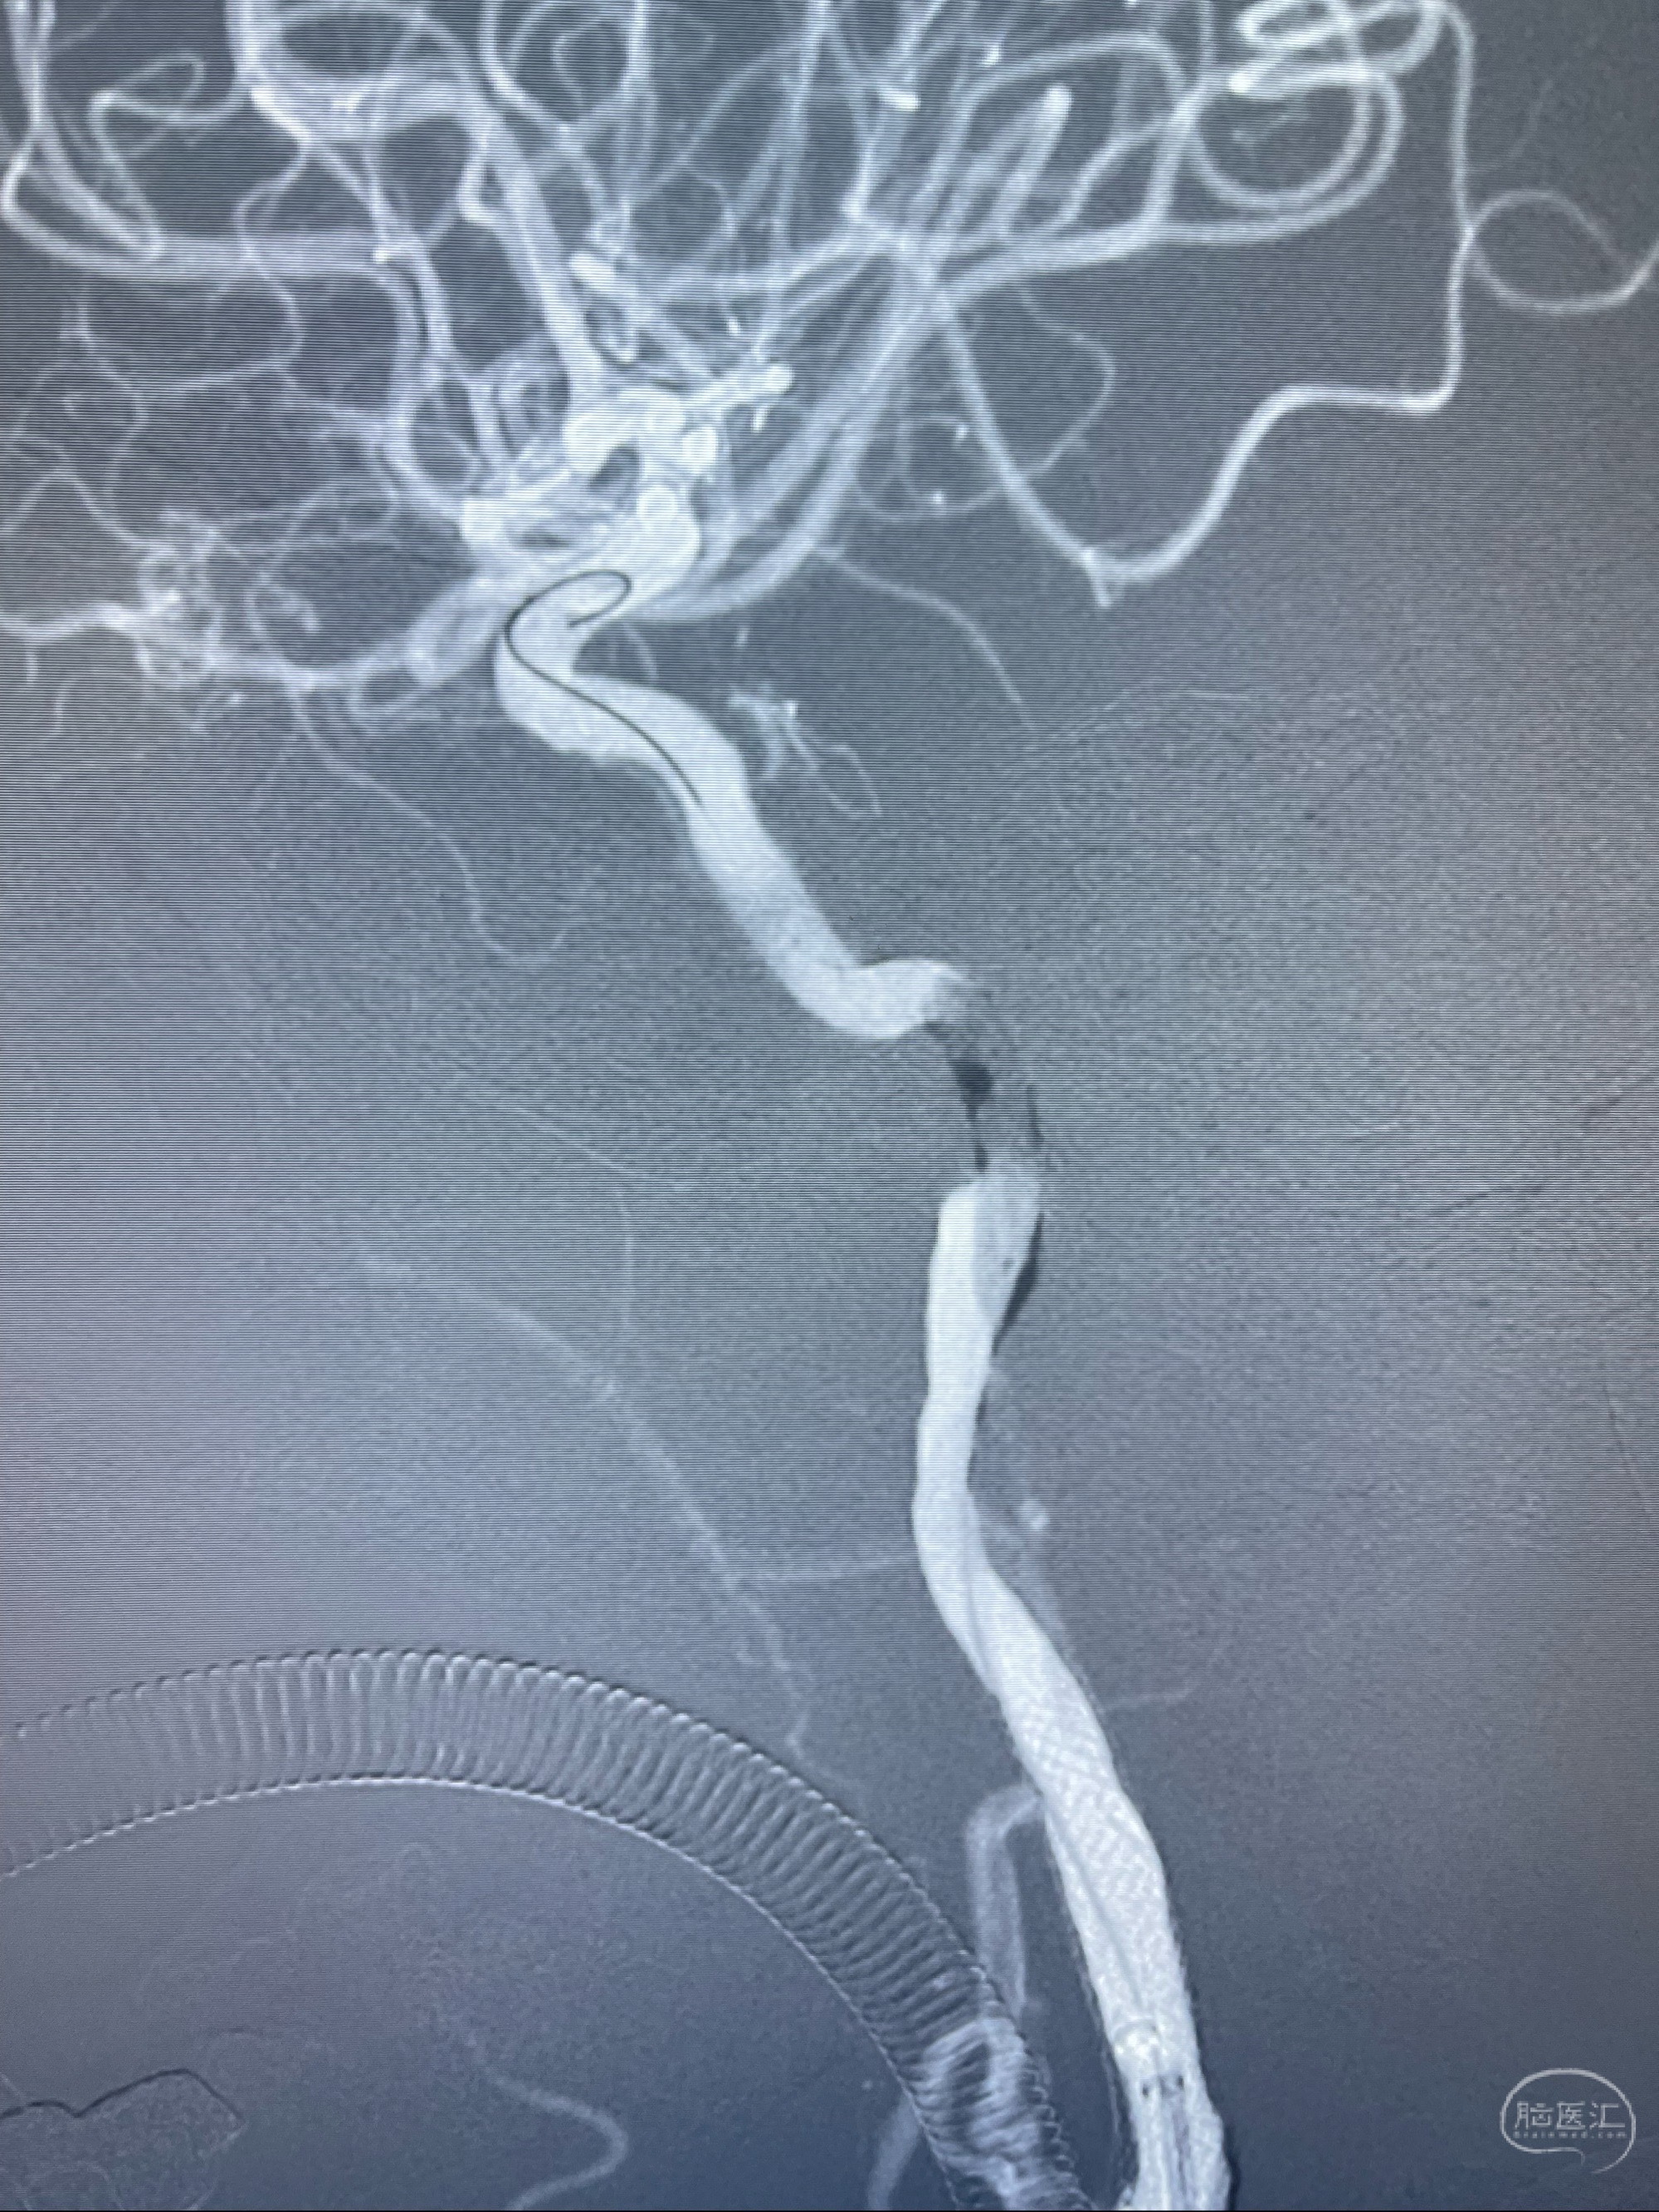

2023-07-10DSA:右侧颈内动脉岩骨段夹层伴中偏重度狭窄改变,左侧颈总动脉闭塞、右侧颈外动脉由右侧肋颈干甲颈干吻合代偿

箭头所示为颈内动脉岩骨段重度狭窄,结合MRI,考虑为肿瘤侵犯右侧颈内动脉

箭头以近至支架段管腔不规则狭窄